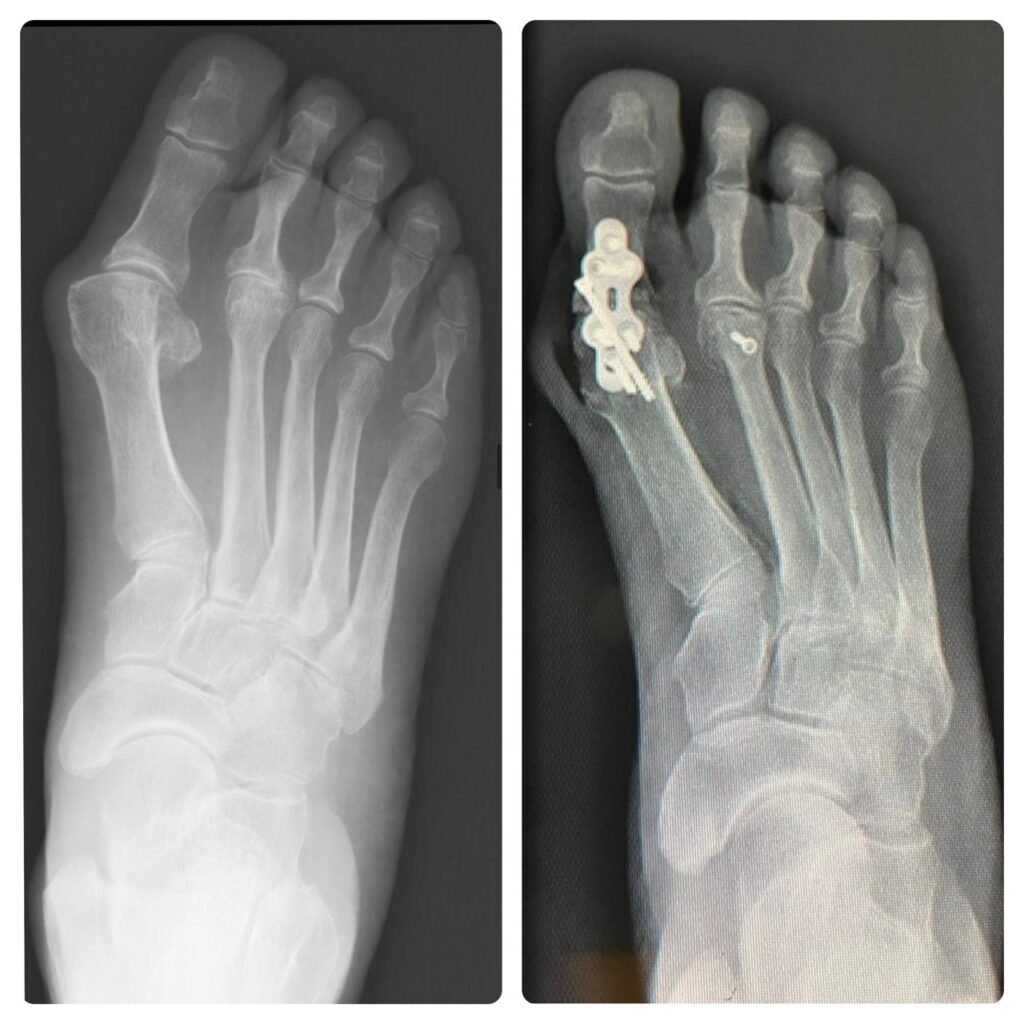

Ofrezco un enfoque integral en traumatología y ortopedia, garantizando atención especializada en cirugía de pie y tobillo, así como en otras condiciones ortopédicas, siempre con el objetivo de mejorar la calidad de vida de mis pacientes

Aspiro a ser reconocido como líder en atención ortopédica en Guadalajara, ofreciendo soluciones innovadoras en cirugía de pie y tobillo. Mi propósito es promover la salud y la movilidad de mis pacientes a través de un servicio excepcional y compasivo.